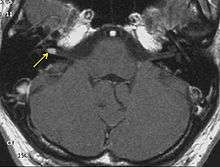

Advances in scanning and testing have made possible the identification of small acoustic neuromas (those still confined to the internal auditory canal). Magnetic resonance imaging (MRI) using Gadolinium as an enhancing contrast material is the preferred diagnostic test for identifying acoustic neuromas. The image formed clearly defines an acoustic neuroma if it is present and this technique can identify tumors measuring down to 5 millimeters in diameter (the scan spacing).